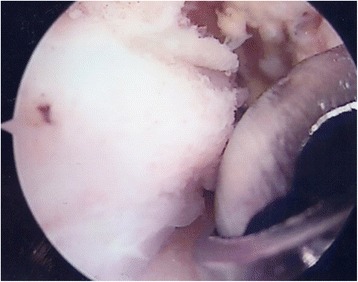

Appropriate bony (Fig. 2) and soft tissue debridement (Fig. 3) was performed to address anterior impingement in all patients using both a mechanical shaver and a radiofrequency probe. Loose bodies were removed in the seven patients; microfractures were undertaken in all instances for management of grade III–IV cartilage lesions. Specifically, after preparation of the cartilage bed, the lesion was measured using a scaled probe. An awl (Condropick, Arthrex, Naples, FL, USA) was introduced with the tip perpendicular to the bed of the lesion (Fig. 4), and the holes were made as described by Steadman, 3 to 4 mm apart and about 2 to 4 mm deep, starting from the center of the lesion to proceed peripherically. The residual stability of the cartilage was assessed, and the irrigation was temporarily stopped to ascertain that marrow fat droplets and blood came out from the holes (Fig. 5).

Fig. 2.

Arthroscopic image showing debridement of bony impingement